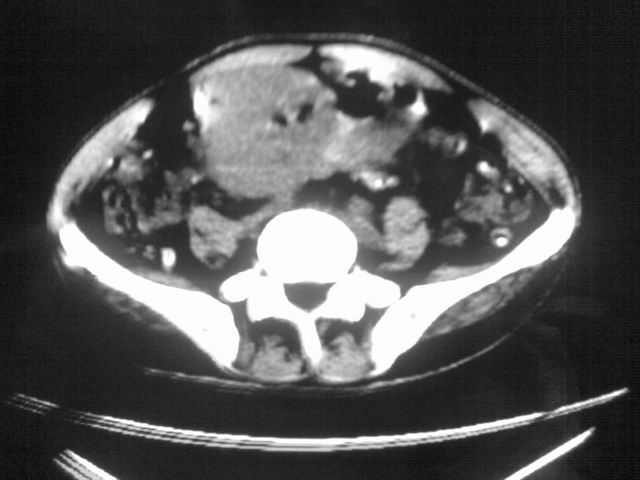

患者m 56岁,盆腔及下腹部胀痛半年,加重1月余,消瘦\中重度贫血.(附:平扫时直肠的高信号为,残留的钡剂).补一下病史:胃镜及纤维结肠镜均无明显异常.

首先是病灶的定位,平扫看很象肠管肿瘤但既然纤维结肠镜正常就可以除外结肠病变,增强成不均匀强化,位于右下腹部应该首先考虑回肠末段占位性病变,1淋巴瘤,2间质瘤,3腹膜后神经原肿瘤待除外,

膀胱后方及直肠前方见巨大混杂密度影,与前列腺相连且向膀胱内突入,精囊腺显示不清;考虑前列腺癌侵犯精囊、膀胱。

膀胱及直肠间有不规侧的软组织密度影,内密度不均匀。其内有坏死囊变,前列腺及精囊腺,膀胱后壁受浸。结合病史考虑腹膜后肉瘤可能性大。